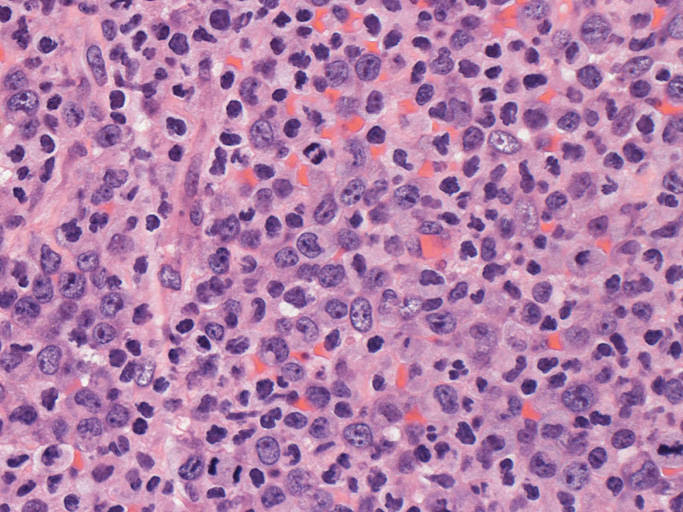

いわゆるanaplastic large cellと呼ぶ多型または腎臓型核をもった大型細胞の増殖はみられない。centroblastに似る円形, 卵円形, わずかに切れ込みをもつ核をもつ大型細胞が索状または地図様に集ぞくし, 背景には淡明な細胞質としわのよったhypercrhomaticな核をもつ細胞がシート状に認められる。二種類の細胞がHEでは認められる。

ALK-positive ALCLのvariant, lymphohistiocytic variantが近いと考える